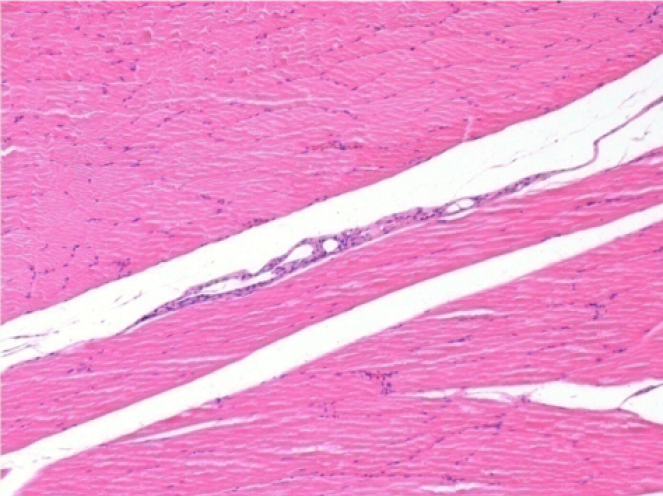

L:Pretibial-No treatment

10 days after Endopeel Injection 0.1ml in the right pretibial muscle.